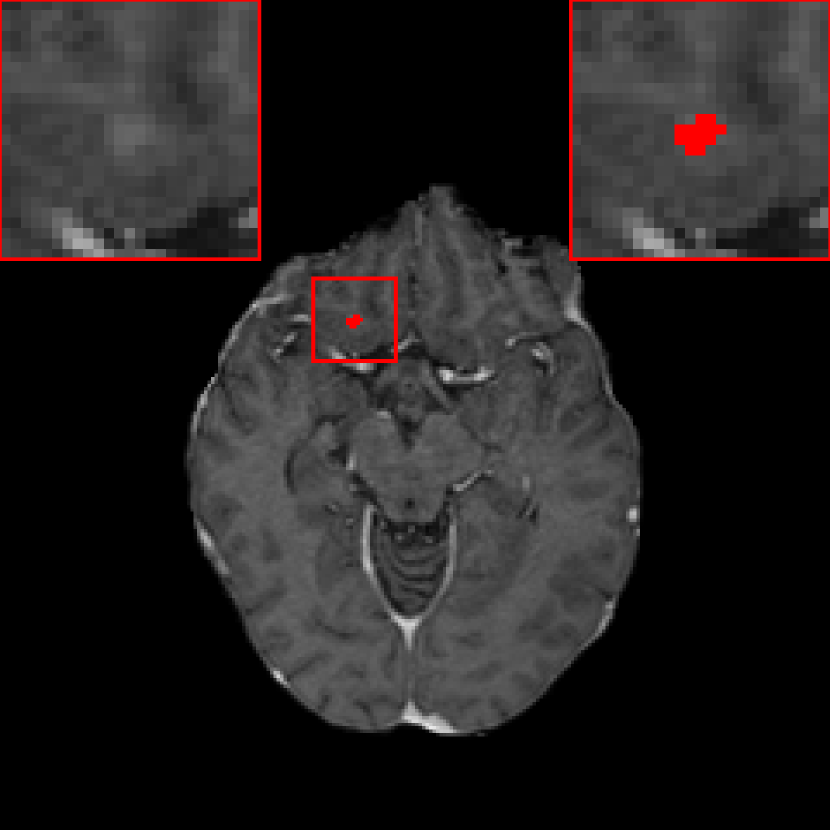

When α𝛼\alpha is decreased in the JVSS loss, the sensitivity is decreased, but the precision is improved. When α=0.9𝛼0.9\alpha=0.9, the sensitivity of DeepMedic with the JVSS loss is comparable to that of DeepMedic with BCE only. However, the precision is increased from 0.691 (237/(237 + 106)) to 0.930 (239/(239 + 18)). When α=0.5𝛼0.5\alpha=0.5, DeepMedic achieves a high precision of 0.987, with only 3 FP metastases remaining. The three FP metastases are displayed in Fig. 5. In Fig. 5, the green region is a TP metastasis and its boundary is segmented well. The red region in Fig. 5 is a FP metastasis, which is a connecting point of two vessels. The right vesicle in Fig. 5 has higher intensity than the surrounding tissues and it has a sphere-like structure in the 3D space. That is why it is falsely detected as a metastasis. The marked region in Fig. 5 has relatively higher intensity than the surrounding vessels. Therefore, whether it is a false or true positive metastasis is controversial, if we look at one single volume only. After checking with the follow-up scans, this region does not grow at all and hence we confirm that it is a FP metastasis.

[Uncaptioned image]

Figure 5: The three false positive metastases detected by DeepMedic with the JVSS (α=0.5𝛼0.5\alpha=0.5) loss are marked by red color. The green region in (a) is a detected true positive metastasis.

III.B. Results of DeepMedic+ using temporal prior

Fig. 5 is an example where temporal prior information is beneficial for metastasis identification. With an additional path for the prior volume, the red region in Fig. 5, as well as the other two cases in Fig. 5, is detected correctly. The sensitivity and precision for DeepMedic+ with the JVSS loss (α=0.995𝛼0.995\alpha=0.995 and α=0.5𝛼0.5\alpha=0.5) together with the temporal prior, i.e. senssubscriptsens\mathcal{M}_{\text{sens}} and specsubscriptspec\mathcal{M}_{\text{spec}} respectively, are displayed in Tab. 1. For α=0.995𝛼0.995\alpha=0.995 (senssubscriptsens\mathcal{M}_{\text{sens}}), the total number of FP metastases is reduced from 247 to 158, where 36.0%percent36.036.0\% ((247 - 158)/247) FP metastases are reduced. The average FP rate per patient is reduced from 2.40 (247/103) to 1.53 (158/103). As a trade-off, the sensitivity has a slight decrease from 0.946 (263/278) to 0.932 (259/278), with only 4 more FN metastases. Note that some of the test volumes are first scans without temporal prior volumes. If we exclude such volumes, the number of FP metastases decreases from 180 to 100 with the help of temporal prior, which is about 44.4% (180 - 100)/180 less, where 3 instead of 4 more FN metastases are observed. The average FP rate per patient is reduced from 2.54 (180/71) to 1.41 (100/71) for those with prior scans. For α=0.5𝛼0.5\alpha=0.5 (specsubscriptspec\mathcal{M}_{\text{spec}}), the sensitivity is slight worse than that of baselinesubscriptbaseline\mathcal{M}_{\text{baseline}}. However, the precision is as high as 0.996 (234/(234 + 1)) with only one FP metastasis. The FP case is displayed in Fig. 7, where the current main image together with its temporal prior and posterior images are displayed. The difference image between the main image and the temporal prior image is displayed in Fig. 7(c), where the area indicated by the arrow has larger difference. That is why specsubscriptspec\mathcal{M}_{\text{spec}} regards this region as a metastasis. However, after checking its posterior image (Fig. 7(d)), no grown metastasis exists. Therefore, we regard the detection in Fig. 7(b) as FP. But we cannot eliminate the possibility that a real metastasis has regressed at the segmented region before the posterior scan.